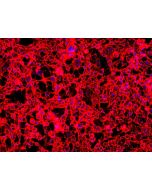

Applications: WB, IHC, IF, FC (Intra), ELISA Observed Molecular Weight: 38-43 kDa

Host / Isotype: Rabbit / IgG Background Information: Serine/threonine kinase which acts as an essential component of the MAP kinase signal transduction pathway. MAPK1/ERK2 and MAPK3/ERK1 are the 2 MAPKs which play an important role in the MAPK/ERK cascade. They participate also in a signaling cascade initiated by activated KIT and KITLG/SCF. Depending on the cellular context, the MAPK/ERK cascade mediates diverse biological functions such as cell growth, adhesion, survival and differentiation through the regulation of transcription, translation, cytoskeletal rearrangements. The MAPK/ERK cascade plays also a role in initiation and regulation of meiosis, mitosis, and postmitotic functions in differentiated cells by phosphorylating a number of transcription factors. MEK1 and MEK2 activate p44 and p42 through phosphorylation of activation loop residues Thr202/Tyr204 and Thr185/Tyr187, respectively. Several downstream targets of p44/42 have been identified, including p90RSK and the transcription factor Elk-1. This antibody simultaneously recognizes the phosphorylation of ERK1 at Thr202 and Tyr204, as well as the phosphorylation of ERK2 at Thr185 and Tyr187.